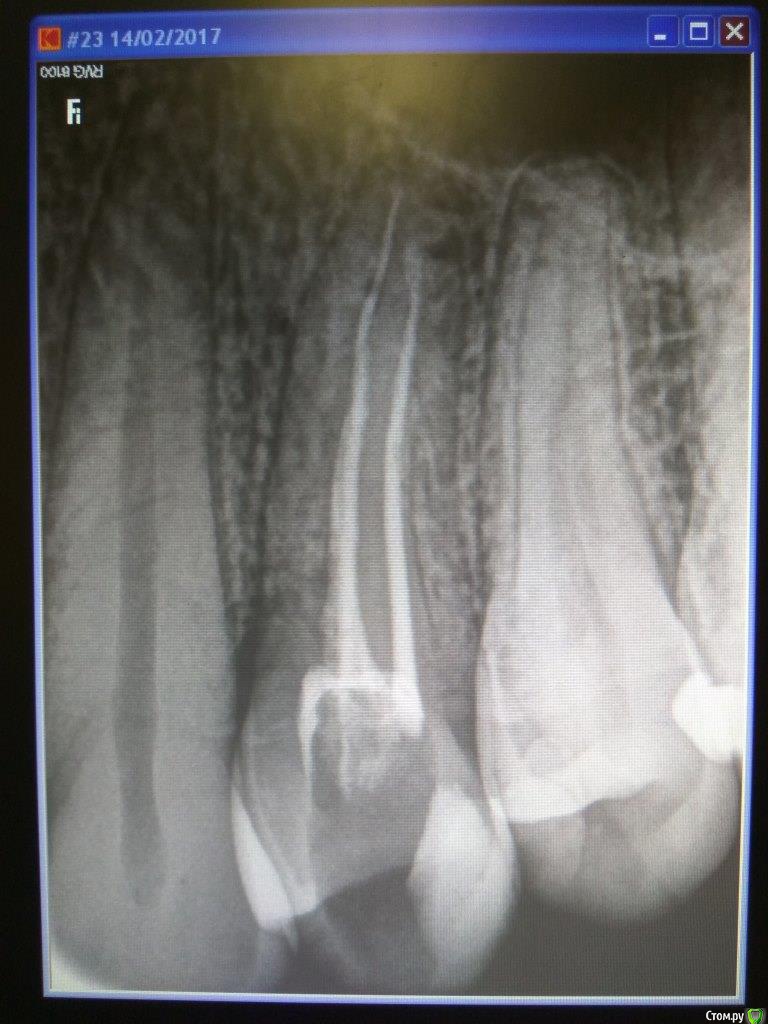

iv.guljaev Опубликовано 28 марта, 2017 Поделиться Опубликовано 28 марта, 2017 Здравствуйте!Года два мучает карман между 3 и 4 зубом верхней челюсти (видно на снимке). Карман уже достаточно большой, часть костной ткани отсутствует. Десна в этом месте часто кровоточит, недавно очень сильно воспалилась (сильная зубная боль, шишка на десне). Карман появился после того как мне залечили 4 зуб - удалили нерв и запломбировали каналы. До этого никаких проблем с десной не было. Стоматолог говорит, непонятно как это лечение могло повлиять на образование кармана - по снимку и осмотру зуб вскрыт сверху, и выхода за боковую поверхность нет.Мнения врачей расходятся:мнение 1) Никакой гранулемы нет. Карман сам не заживет, т.к. отсутсвует часть костной ткани. Для лечения кармана необходима пересадка костной ткани. Однако никаких гарантий, что приживется, нет. Грубо говоря 50/50. Если не получится, нужно удалять зуб (или со временем сам выпадет) и ставить имплант.мнение 2) "на корне гранулема 3-4 мм, видно невооруженным глазом". Пока ее не вылечить, с карманом что-то делать бесполезно. Необходимо перелечить каналы и хорошо восстановить коронковую часть и контактный пункт. Гранулему необходимо лечить 3-5 месяцев с выведением лекарства за верхушку. Есть ли гранулема?Могла ли она стать причиной образования кармана?Нужно ли перелечивать каналы?Как лечить карман? От вашего мнения зависит стратегия лечения, которую я выберу. Спасибо за вашу работу! Ссылка на комментарий

Dok22 Опубликовано 30 марта, 2017 Поделиться Опубликовано 30 марта, 2017 Очень похоже на трешину. Ссылка на комментарий

iv.guljaev Опубликовано 2 апреля, 2017 Автор Поделиться Опубликовано 2 апреля, 2017 Очень похоже на трешину.В смысле трещина в зубе? И из-за этого гранулема и карман? Как можно подтвердить наличие трещины? (после 3 консультаций ни один стоматолог не упоминал о трещине) Как посоветуете поступить - сделать еще один снимок или что-то еще? Ссылка на комментарий